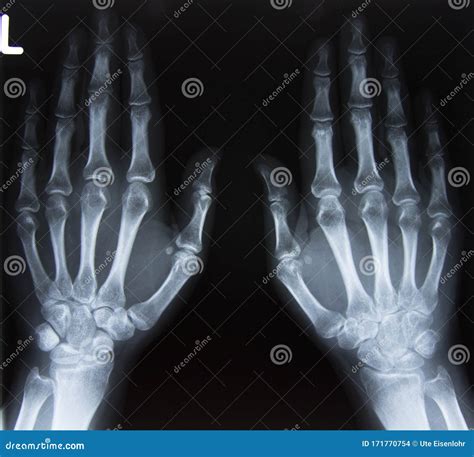

The wrist is a complex structure composed of multiple bones, ligaments, and tendons. It connects the hand to the forearm and allows for a wide range of movements. The primary bones in the wrist include:

• Carpal Bones: There are eight carpal bones in the wrist, arranged in two rows. These bones are small and irregularly shaped, providing stability and flexibility to the wrist.

• Metacarpal Bones: These five bones connect the carpal bones to the phalanges (finger bones).

• Radius and Ulna: These are the two bones of the forearm that articulate with the carpal bones to form the wrist joint.

• Arthritis: Osteoarthritis and rheumatoid arthritis can affect the wrist joints, causing pain and stiffness.